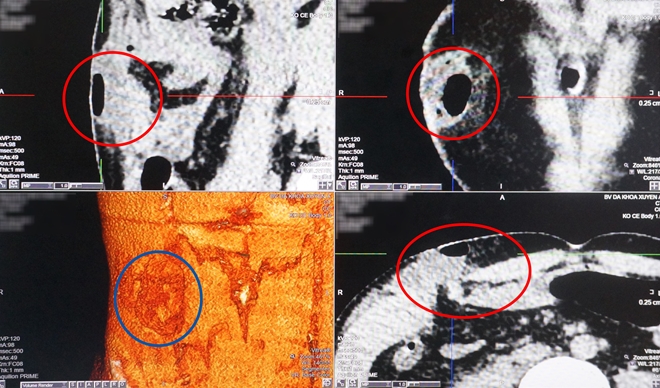

Màng tim xơ như 'mo cau' suýt lấy mạng người đàn ông

19:03 12/01/2018

Đó là trường hợp bệnh nhân V.T.T (55 tuổi, ngụ Hóc Môn, TP.HCM), được bệnh viện đa khoa Xuyên Á (BVXA) thông tin vào ngày 11-1-2018. Bệnh nhân đã được điều trị thành công dù ca phẫu thuật rất khó khăn.